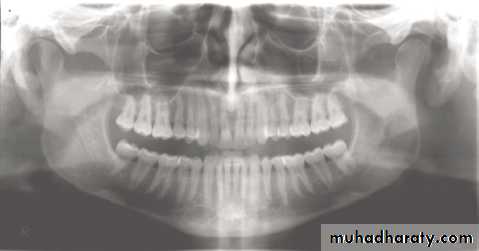

In a good panoramic radiograph:

The mandible is “U” shaped.

The condyles are positioned about equal distance from the inside edges of the image and 1⁄3 of the way down from the top edge of the image.

The occlusal plane exhibits a slight curve or “smile line,” upwards.

The roots of the maxillary and mandibular anterior teeth are readily visible with minimal distortion.

Magnification is equal on both sides of the midline.